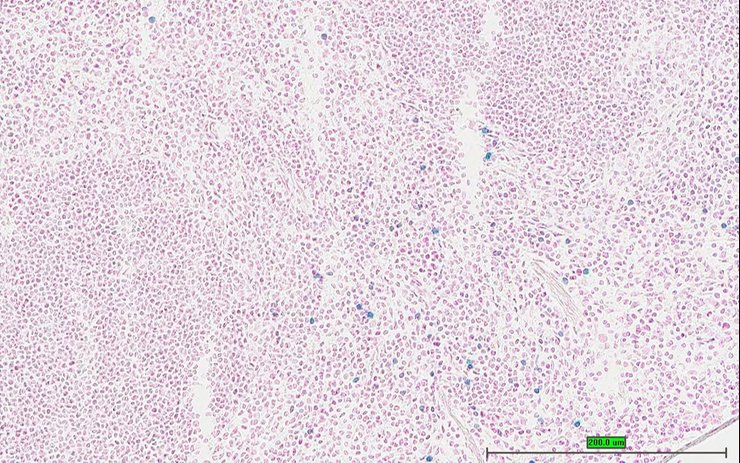

TS28: spleen Present UC Davis_1883588

Specimen UC Davis_1883588: postnatal adult; Prf1tm1.1(KOMP)Vlcg/Prf1+ (more )